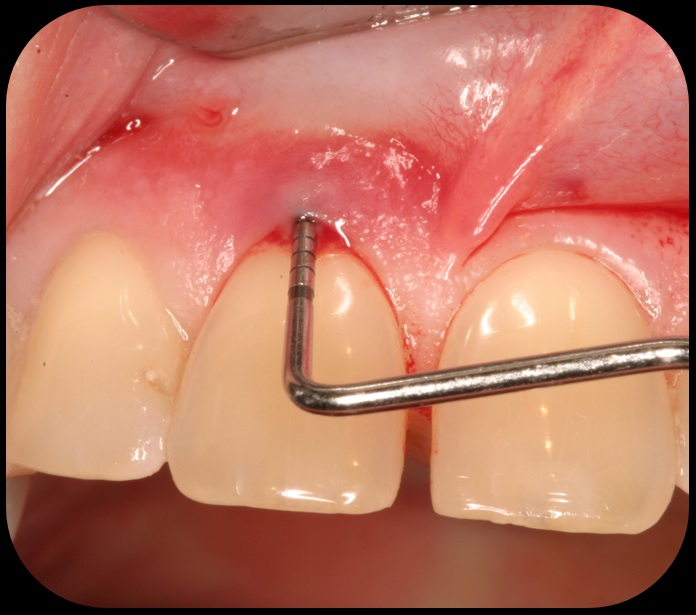

Severe periodontitis lesion.

Fig. 2

Then, too, are opportunities to prepare the site for regeneration by coupling therapies, applying an enamel matrix derivative, along with traditional bone grafts of demineralized freeze-dried bone allograft; potentially, gains in attachment with minimal probing depth and retained papilla may avoid the need for an implant (Figure 2 through Figure 7).